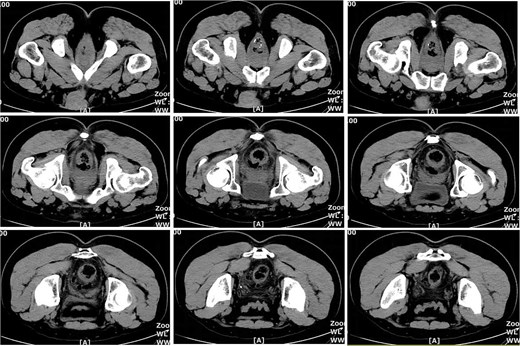

On postoperative Day 10, a repeat complete blood count showed a white blood cell count of 9.74 × 109/l and a neutrophil percentage of 69.5%. The patient’s temperature ranged between 36.4 and 37.4°C, and abdominal discomfort was partially alleviated. A follow-up pelvic CT scan revealed a breach in the anterior rectal wall with gas density shadows communicating with the surrounding area, accompanied by filamentous exudate density shadows and multiple gas density shadows (Fig. 2). These findings indicated rectal wall edema and anterior wall perforation with surrounding infection. Anorectal examination revealed a 0.5 × 0.5 cm ulcerative lesion at the 5 o’clock position of the anastomosis site in the knee–chest position. This was considered rectal perforation secondary to anastomotic dehiscence. Given the absence of peritoneal irritation signs and normalization of the white blood cell count, a conservative treatment plan was adopted after discussion with the patient. This plan involved continuing anti-infective treatment with intravenous cefoperazone sodium and sulbactam sodium.